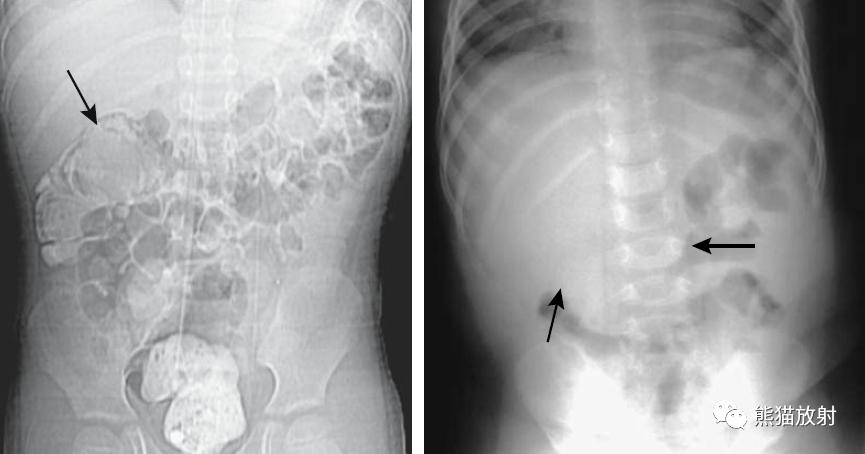

回-结肠套叠。CT定位像示7岁患儿的肠套叠(箭头)。Burkitt淋巴瘤所致。右图:10个月大的婴儿,疼痛和右上腹肿块。X线平片示横结肠(箭头)区域有软组织肿块。钡灌肠证实为肠套叠。